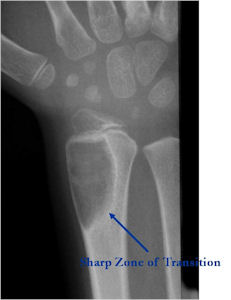

Plain X-rays:

- Geographic, circumscribed lesion usually around 5cm in size.

- There may be expansion of bone, cortical thinning and cortical breakthrough. A soft tissue mass may accompany this lesion but the soft tissue component is usually contained by the periosteum.

- The periosteum remains intact around the soft tissue component. Might need a CT scan to detect the subtle calcification (Egg Shell Rim of Calcification) associated with an intact periosteal reaction

- The lesion may be entirely radiolucent but usually shows some degree of mineralization. Mineralization may appear stippled like cartilage but do not see chondroid pathologically. Mineralization is sometimes better detected on a CT scan rather than an x-ray.

- Usually less surrounding sclerosis than an osteoid osteoma.